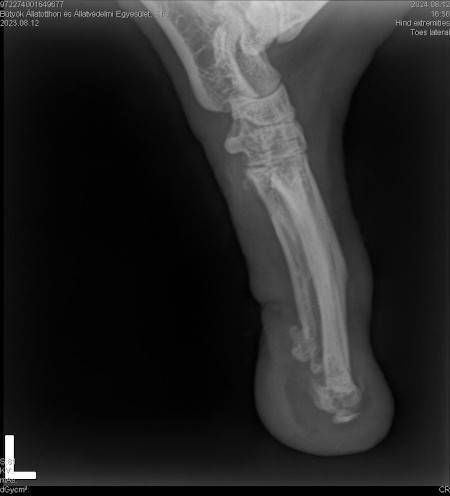

Ellie ist ca. 1 Jahr alt (Stand 08/2024) und hat bereits eine bewegte Vergangenheit hinter sich. Nach 5 Tagen intensiver Versuche konnte sie endlich von der Strasse gerettet werden, wo sie hungrig, durstig und in einem schlechten gesundheitlichen Zustand allein und orientierungslos umherirrte. Elli war von Flöhen und Zecken geplagt und stark abgemagert, doch trotz all dieser Herausforderungen zeigt sie einen unglaublichen Lebenswillen. Elli hat ein Handicap: Ihr fehlt ein Fuß am Hinterbein. Ob dies auf einen Unfall oder eine angeborene Fehlbildung zurückzuführen ist, wissen wir nicht. Doch Elli lässt sich davon nicht einschränken! Sie zeigt sich flink und steckt voller Energie. Ellie kommt erstaunlich gut mit ihrem Bein zurecht, es stört sie in keiner Weise und sie kann problemlos laufen, spielen und sogar rennen. Dennoch benötigt sie einen Schutz für ihren Stummel, entweder eine passende Prothese oder einen gefütterten Silikonschuh. Dies sollte in ihrem neuen Zuhause gründlich tierärztlich abgeklärt werden. Trotz ihrer Vergangenheit ist Elli eine unglaublich liebe, verschmuste und fröhliche Hündin. Sie liebt die Nähe zu Menschen, ist sehr anhänglich und versteht sich gut mit anderen Hunden. Ihre neuen Menschen sollten Freude daran haben, ihr alles ruhig und geduldig beizubringen, was so ein junges Mädel für ihr weiteres Leben als Familienhündin wissen muss. Ebenso sollten sich die neuen Besitzer bewusst sein, dass ein Hund nicht nur Freude, sondern auch jede Menge Arbeit und Verantwortung mit sich bringt, damit Ellie sich zu einer tollen Begleiterin entwickeln kann. Für unsere Herzensbrecherin suchen wir ein liebevolles, fürsorgliches und dauerhaftes Zuhause, wo sie nebst viel Spass auch abwechslungsreiche Spaziergänge erleben darf, wo sie artgerecht ausgelastet wird und täglich die Zuwendung und Pflege bekommt die sie verdient. Wer erfüllt den Traum von unserer Zuckerschnute Ellie und gibt ihr trotz ihres kleinen Handicaps die Chance ein treues Familienmitglied zu werden?